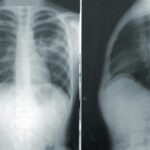

- 高齢者の肺炎と初期症状に注意!重症化を防ぐためのポイント高齢者がかかる肺炎は、初期症状が分かりにくく、気づいたときには重症化しているケースが少なくありません。特に、免… 続きを読む: 高齢者の肺炎と初期症状に注意!重症化を防ぐためのポイント